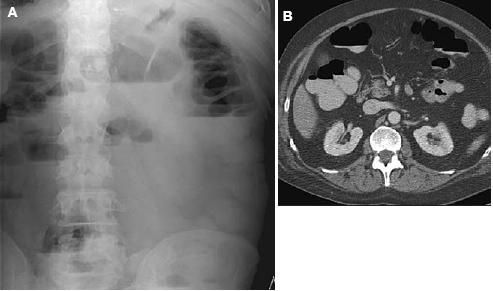

Physical examination revealed no bowel sounds, diffuse abdominal tenderness, blood pressure of 158/102 mm Hg, pulse of 98 beats per minute, temperature of 37°C (98.6°F), and no respiratory distress. An intestinal obstruction series and a CT scan of the abdomen showed an ileus but no obstructing mass (Figure 1).

Figure 1 – An intestinal obstruction series (A) and a CT scan of the abdomen (B) showed an ileus but no obstructing mass.